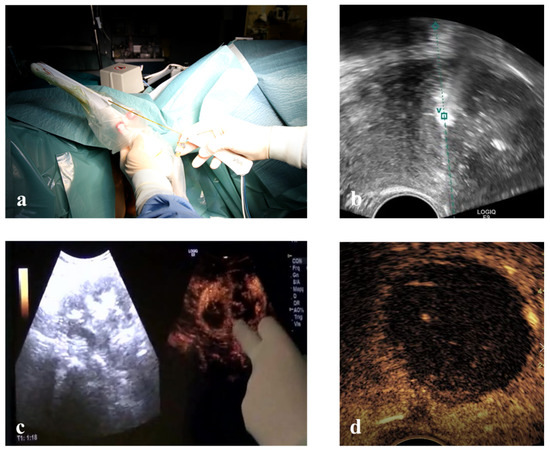

This prospective study enrolled 54 consecutive patients. RFM was performed in three ways: Vaginal Ultrasound-guided RFM (VU-RFM), Laparoscopic RFM (L-RFM) and Hysteroscopic-RFM (H-RFM). These three methods of myolysis were performed both separately as an exclusive type of surgery and in a combined approach when the localization of the myomas required to use the same electrode through different access routes. The ablation device consisted of an RF energy generator (STARmed, VIVA RF generator VRS01, Gyeonggi-do, Korea 10355) and an electric pump for the continuous cooling of the electrode tip. The RF generator to which the electrode (STARmed Gyeonggi-do, Korea 10355) was connected simultaneously displayed the temperature of the electrode tip, the tissue impedance characteristics, the power and the ablation time. A 35 cm long 17G internally cooled electrode with an exposed tip of 10 mm or a variable exposed tip was used (Figure 1).

Pre-treatment evaluation was performed for all patients with conventional trans-abdominal and transvaginal (TV) ultrasound using an ultrasound machine equipped with a 3–5 MHz convex probe and a 1–6 MHz trans-vaginal probe (Logiq E9, GE Healthcare, Milwaukee, WI, USA). Contrast-enhanced ultrasound (CEUS) evaluation was also performed for all patients after the intra-venous injection of SonoVue micro-bubbles contrast (4.8 mL; Bracco, Milan) to evaluate the vascularity of myomas (Figure 1). The micro-bubble contrast agent was mixed with 5 mL of normal saline solution and was administered via rapid bolus into the median cubital vein, followed immediately by 5 mL of normal saline solution.

Immediately before ablation, all patients were subject to a US-guided core-needle biopsy of all fibroids to be treated by 18 Gauge Bard Max-Core disposable core biopsy instruments (#MC1820, Bard Limited Crawley, UK) (Figure 1). At least two biopsies were taken for each myoma, but the number of biopsies changed according to the size of the fibroid (one biopsy per centimeter of fibroid) so that all areas of the fibroid could be evaluated. All tissue samples were sent to the Institute of Pathology for routine analysis, and all samples were classified as representative by pathology.

Figure 1. (a) 35 cm long 17 Gauge radiofrequency electrode at the left of the table and an 18 gauge disposable core biopsy instrument at the right. (b) Contrast-enhanced ultrasound (CEUS) evaluation before radiofrequency ablation of a fibroid. (c) Hyperechogenic line within the myoma viewable during the biopsy (arrowheads). (d) CEUS evaluation after radiofrequency (RF) ablation demonstrates no residual contrast enhancement within the fibroid (asterisk).